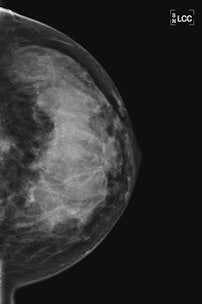

| 45-year-old asyptomatic woman with family history of breast cancer underwent mammography and MRI for screening. Full field digital mammogram is normal. Coned down view was done after MRI. MRI depicts a well circumscribed tumor with fast and early enhancement, strong wash out, and peripheral (rim) enhancement. This is high grade invasive cancer (basal-like) without calcifications; even coned down view is unremarkable. All images courtesy of Dr. Christiane Kuhl |